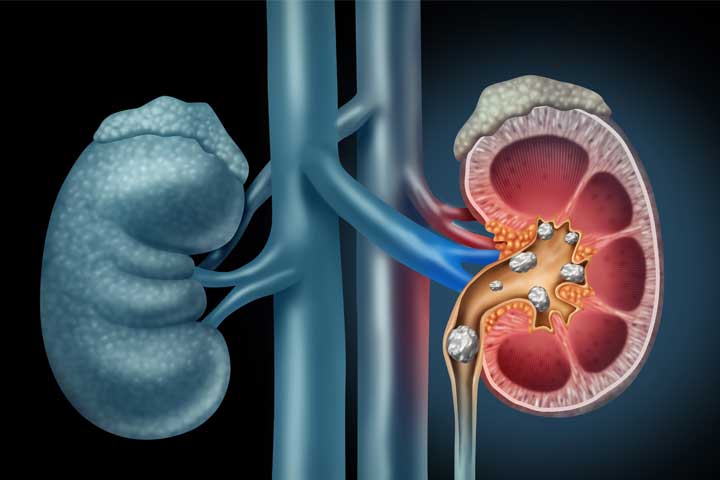

Kidney stones are hard deposits of minerals and acid salts that stick together in concentrated urine. They can be painful when passing through the urinary tract but usually don't cause permanent damage. The most common symptom is severe pain, usually in the side of the abdomen. Regarding treatment for Kidney Stones from HiiMS- we suggest certain postural therapies to get the best possible help.

Kidney Stone

Kidney stones are hard deposits of minerals and acid salts that stick together in concentrated urine. They can be painful when passing through the urinary tract but usually don't cause permanent damage. The most common symptom is severe pain, usually in the side of the abdomen, often associated with nausea. Regarding treatment for Kidney Stones from HiiMS- we suggest certain postural therapies to get the best possible help.

Is it true that Ayurvedic procedures and medications can effectively prevent the development of kidney stones?

Indeed, Ayurvedic therapies such as panchakarma, head tilt down, and others have demonstrated encouraging outcomes in individuals experiencing symptoms of kidney stones. The Ayurvedic formulations employed in these treatments aid in restoring the normal functioning of the kidneys and effectively prevent the formation of kidney stones.

What therapies are recommended by doctors for the removal of kidney stones?

Ayurvedic therapies like Panchkarma, Head Tilt Down, Lower Leg Emulsion, and Hot Water Tub are known to be highly effective in the removal of kidney stones.